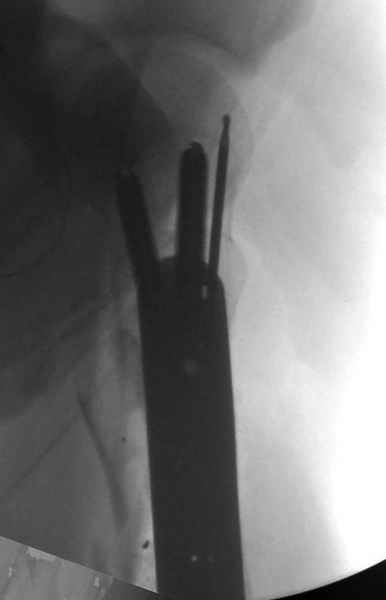

Молодой, с общим состоянием без проблем. Больной соперирован в день поступления и через два дня после операции выписан, так что не успел развиться гной.

Перелом низкоскоростным оружием, типа пистолетного, так что не стали гоняться за пулевыми фрагментами. С нервом пока подождем, иногда нерв восстанавливается если не прямое попадание в нерв, а "сотрясение" (shock wave injury).

Из всех типов фиксации взяли малоинвазивную технику мостовидной пластиной, использовали Locking проксимальную Synthes пластину.

Djoldas Kuldjanov, MD

Department of Orthopedic Surgery

St. Louis University Medical Center